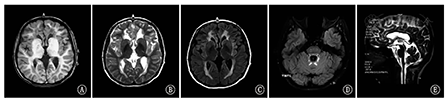

例4,女,31岁,尚未出现临床症状。28岁时由于其女儿诊断为Ⅰ型AxD患儿,基因检测发现GFAP杂合突变(c.1154 C>A,p.Ser385Tyr)来源于母亲。其头颅MRI(31岁)示双侧脑室前后角旁白质对称性T1WI低、T2WI高、T2FLAIR高信号,小脑白质T2FLAIR点片状高信号,延髓、颈髓较细,胼胝体体部较薄(图4)。

注:A、B分别为T1加权像及T2加权像轴位;C、D为T2液体衰减反转恢复序列图像轴位;E为T2WI矢状位 A,B:Axial T1 weighted imaging,T2 weighted imaging;C,D:T2 fluid attenuated inversion recovery imaging;E:sagittal T2WI